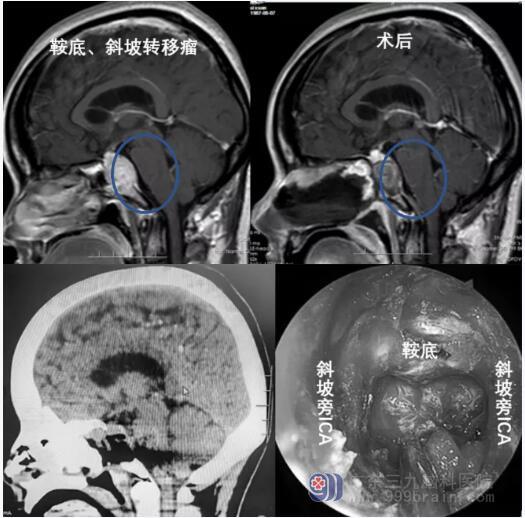

侵犯斜坡肿瘤

由于斜坡肿瘤主要发生于中线部位,开颅手术常常难以达到全切。目前,神经内镜下经鼻入路也已用于中线颅底脊索瘤的治疗。神经内镜经鼻切除可以实现直接经硬膜外入路,降低颅神经麻痹和颅内并发症的发生率。